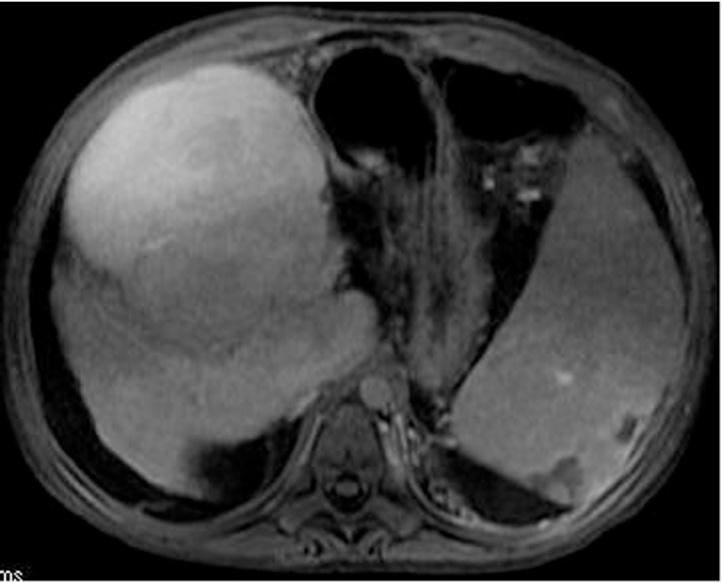

CONCLUSION

The presence of a large hepatic nodule Alagille syndrome can be benign in these patients also predisposed to hepatocellular carcinoma. Therefore, cautious evaluation with magnetic resonance imaging study before liver transplantation is mandatory.

结论

在这些也易患肝细胞癌的患者中,阿拉吉尔综合征中出现的大肝脏结节可能是良性的。因此,肝移植前必须用磁共振成像研究进行谨慎评估。